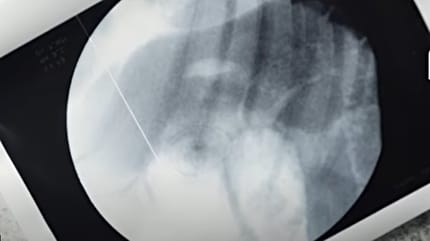

Röntgenbild des Hundes

Der Hundehalter reagiert blitzschnell und bringt den schwer verletzten Friedwart umgehend zum Tierarzt. In einer dramatischen dreistündigen Not-Operation öffnet der Veterinär den Bauch des Tieres, um die Rasierklinge aus dem Magen zu entfernen.

Ein großes Stück der Klinge wird gefunden, doch noch immer fehlt ein Teil. Die Sorge: Es könnte noch immer im Körper des Hundes stecken und weitere Verletzungen verursachen.

„Der Hund wird jetzt engmaschig betreut und überwacht“, erklärte der behandelnde Tierarzt gegenüber bild.de. Außerdem bekommt Friedwart nun Sauerkraut mit Speck, in der Hoffnung, dass das noch fehlende Stück der Rasierklinge so auf natürlichem Weg ausgeschieden wird.